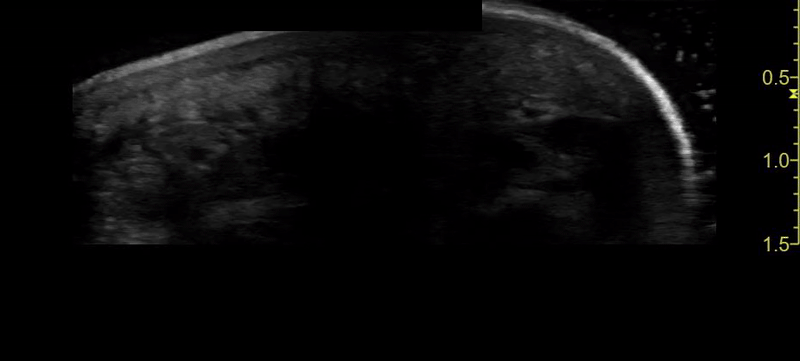

POCUS soft tissue shows a hyperechoic foreign body in long axis that measured approximately 1.4 cm.

SONO PEARLS: POCUS can be key for detecting foreign objects that are radiolucent on radiographs, such as wood, plastic, or organic material. A water bath in ultrasound imaging improves visualization of superficial skin by acting as a conductive medium. Water’s low attenuation allows for ultrasound waves to travel farther with minimal image degradation. Its acoustic properties enhance resolution and help reduce artifacts. In this case, the foreign object that was a mere 5mm from the skin was easily visualized.